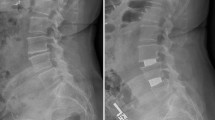

The DICOM files were imported into Mimics® (version 17.0, Materialise, Leuven, Belgium) to measure CSAs of the ES, QL and IP at each lumbar disc level from the T12–L1 through the L5–S1 (Fig. 1). Due to difficulties in discriminating between the multifidus (MF), longissimus and iliocostalis muscles on images, these muscles are usually considered as one muscle mass, i.e., erector spinae (ES) [23]. For patients and as needed in the detailed biomechanical models, the multifidus muscle was, however, carefully isolated using the fascial border separating it from the more laterally located longissimus [24]. No attempt was made to separate longissimus and iliocostalis muscles as their boundaries were less clear to identify in most images [25]. Three trained raters, blind to each other’s measurements, traced outer fascial boundaries of each muscle using a mouse-guided tool while excluding extramuscular fat and connective tissues. Subsequently, the software calculated the encompassed area within the traced boundary of each muscle (i.e., geometrical CSA including intramuscular noncontractile tissues).

The PROFILE LINE and THRESHOLD functions used in Mimics® to determine lower and upper limits of pure normal muscle signal intensity for MF at the L4–L5 level of the same patient (Fig. 1) a before and b after surgery. The distinction between contractile and noncontractile components of each muscle at each level was made using the signal intensity of the pixels for each subject at each MRI session. For this, the PROFILE LINE function was initially used to measure signal intensity along several user-defined lines passing through different tissues including pure muscle, intramuscular fat, connective tissues and extramuscular fats (Fig. 2). From these, while varying for each subject at each MR session, the lower and upper limits of pure normal muscle signal intensity were determined to be, respectively, ~300 (lower limit) and 800 (upper limit). Subsequently, the THRESHOLD function was used within the border of each muscle to exclude tissues whose signal intensities were out of this range (i.e., noncontractile components such as intramuscular fat and connective tissues) (see Fig. 3)

Exclusion of intramuscular noncontractile components from the total CSA of MF at the L4–L5 level of the same patient (Fig. 1) a before and b after surgery (pixels corresponding to contractile components are highlighted)